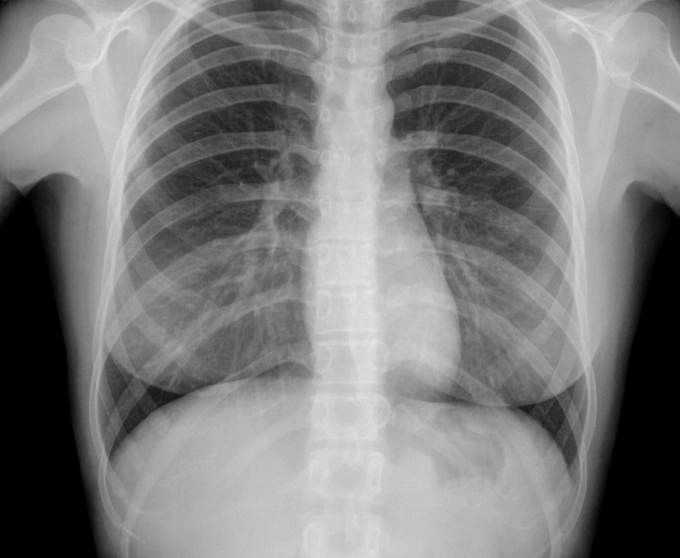

На 16 декември, в петък, от 14.00 до 16.00 часа, д-р Иво Станчев ще преглежда в "Медицински център-1-Севлиево", съобщават от там. Д-р Станчев е специалист пулмология и фтизиатрия от СБАЛ по белодробни болести гр. Габрово. Прегледите са с направление от личния лекар или срещу заплащане, но с предварително записване на регистратурата на центъра.

В сезона на вирусите, когато усложнениято от грип и инфекции за доста чести, не пропускайте да потърсите специалист по белодробни болести, съветват медиците.